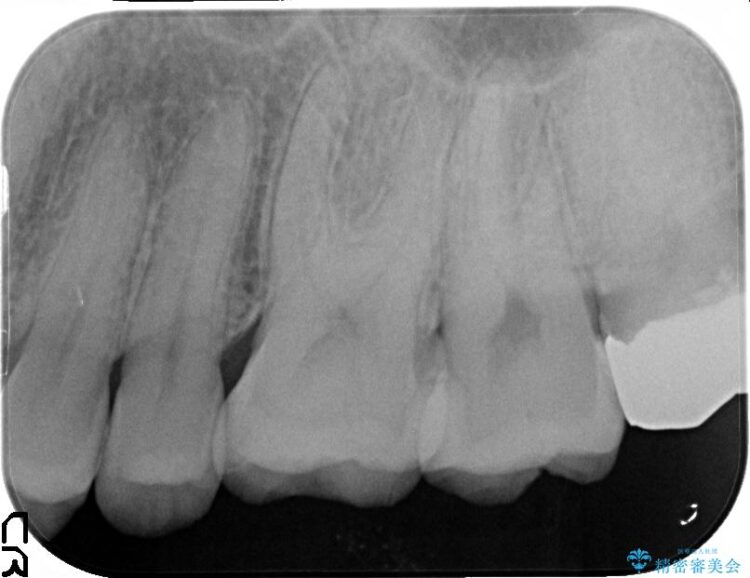

古い詰め物を外し、白く審美性の高いセラミックインレーにて再治療を行うこととしました。

今回は保険で治療してあった銀歯を審美性からセラミックインレーにて再度治療しました。

保険で治療した銀歯は、経年劣化で詰め物のふちが欠けたり、適合が悪くなり詰め物の下など目に見えない部分の虫歯の原因となることがあります。また、金属のため口にするものの熱の影響を受けやすく成分が溶けやすくなったり、変形してしまうことがあります。

セラミックスは、見た目の審美性だけでなく劣化がしにくいことや金属アレルギーのリスクがないことがメリットとしてあげられます。